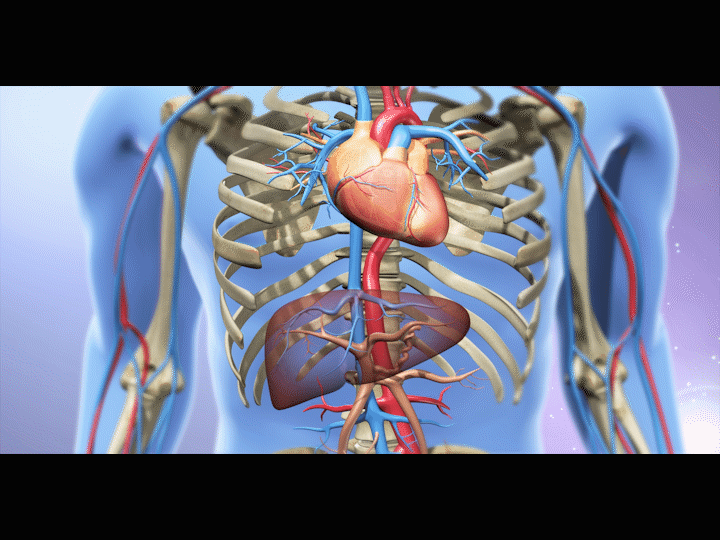

经颈静脉肝内门体静脉分流术(tips)

图片尺寸690x332